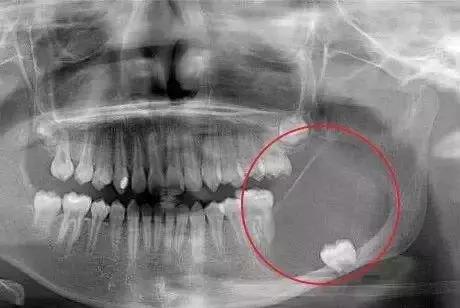

智齿引发的牙源性囊肿或肿瘤

这部分多说几句,有人可能不明白看不见摸不着的智齿咋就囊肿了?

停留在牙槽中的智齿会刺激上皮细胞,使它增殖并分泌液体,当分泌的液体慢慢增多时,会像气球那样鼓胀起来,逐渐形成颌骨囊胀。

颌骨囊肿一开始可能没有疼痛感,再加上没有做牙齿检查的习惯,很多人都是拖到出现肿痛才发现。

还能救的囊肿可以采取了开窗的治疗办法,原理就是因为颌骨囊肿很大,像个气球一样。可以在颌骨囊肿上打一个洞,让‘气球’里面的气体跑出来。等它缩小到一定程度的时候,可以直接把颌骨囊肿摘掉,这样左下颌的骨头能够保留下来,不至于毁容。

严重的就得把下颌骨头切掉,那样会导致面部塌陷,甚至有毁容的可能。